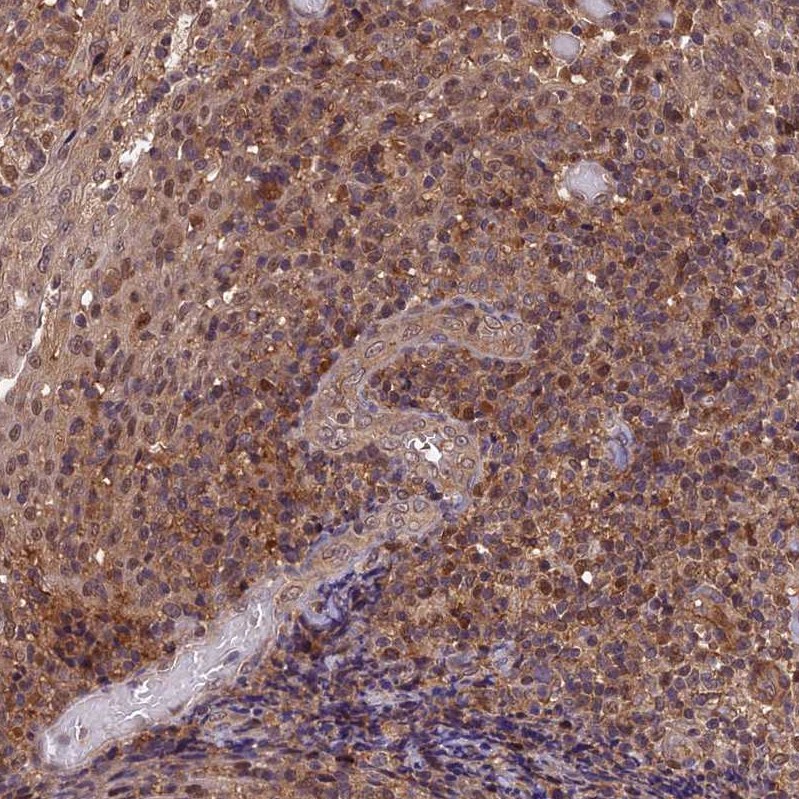

Immunohistochemical staining of human liver shows moderate cytoplasmic and nucleus positivity in hepatocytes.